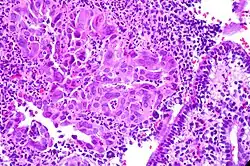

Die Zervizitis, Cervicitis (von Cervix für Gebärmutterhals) oder Gebärmutterhalsentzündung ist eine Entzündung des Gebärmutterhalses.[1][2]

Klinische Erscheinungen

Klinische Kriterien sind:[1][3]

- Blutungen und vaginaler Ausfluss (Fluor vaginalis).

Bei zusätzlicher Kolpitis können entsprechende Symptome hinzutreten.

Breitet sich die Infektion weiter aus, kann sich eine Endometritis und Salpingitis entwickeln.

Als Komplikation kann es zu einer Pelvic inflammatory disease (PID) mit eventueller Unfruchtbarkeit, chronischen Schmerzzuständen im Becken oder einer Extrauteringravidität kommen. Infektionen mit HPV gelten als Präkanzerose für Zervixkarzinome.[4]

Diagnose

Die Diagnose ergibt sich aus Kolposkopie mit Abstrich, der Infektionserreger kann mittels PCR oder HPV-DNA-Tests bestimmt werden.[1]